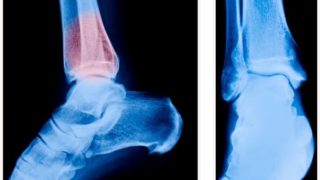

骨刺或骨赘是凸出的额外骨骼。它们是由于持续的压力…